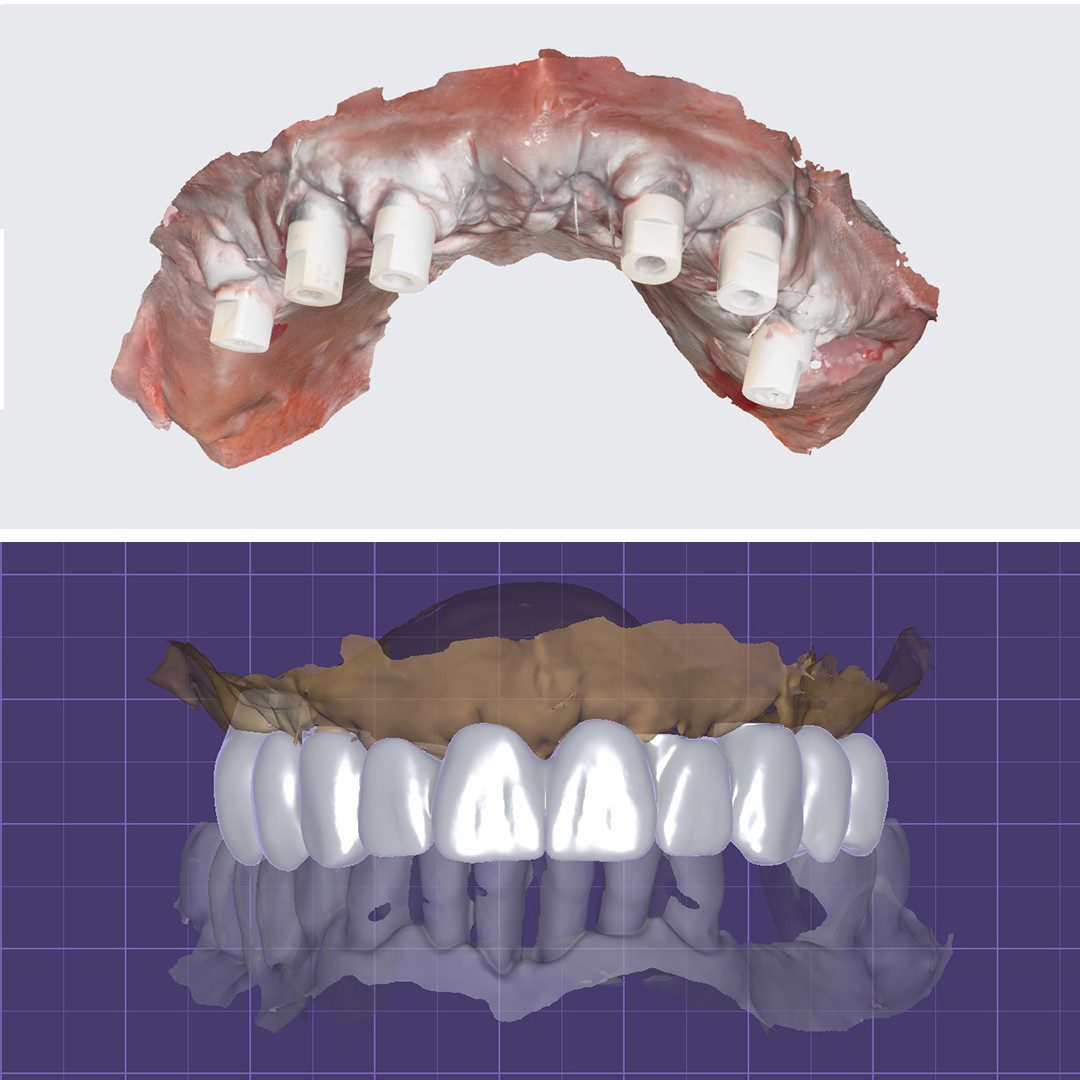

- Amprentare digitală cu scanner intraoral

- Aplicare lucrare provizorie pe implanturi